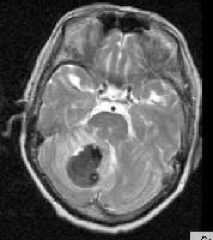

![геморрагический инсульт]()

МРТ головного мозга. Аксиальная Т2-взвешенная МРТ. Кровоизлияние в мозжечок.